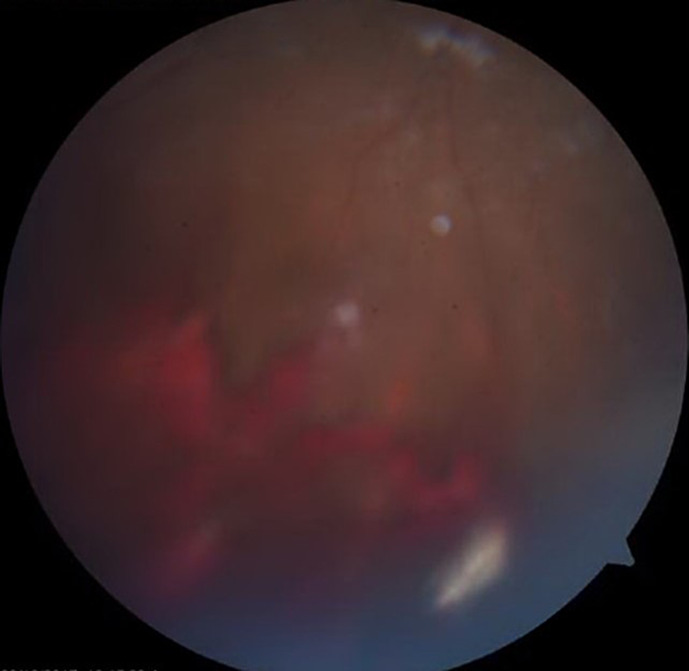

Case presentation: We report a case of a 7-year-old girl with a retained intraocular graphite pencil lead foreign body in the vitreous treated conservatively for more than 5 years without any consequences.

Conclusion: Graphite foreign bodies may be retained in the eye posterior segment without causing any inflammation or damage to the intraocular structures.